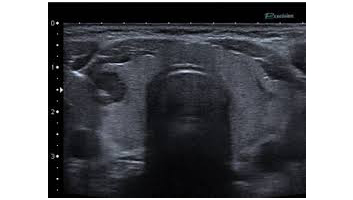

- Musculaire, tendineuse, articulaire, thyroïdienne, cervicale.

- Echographie mammaire